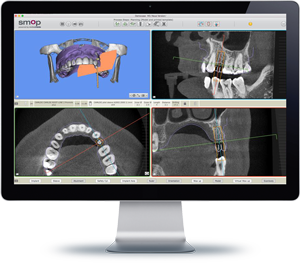

コラム「excad(エクゾキャド)」による3D

画像

当院では、治療精度を向上するために「excad(エクゾキャド)」を導入しています。excadはデジタル技術を活用して、インプラントの設計からプランニングを行うことができるソフトです。このソフトを利用することで、お口を3Dで把握することができ、インプラントの正確な設計位置決めが可能になります。

治療計画を正確に行えるため、無駄な治療を省くことができ、治療期間の短縮にもつながります。